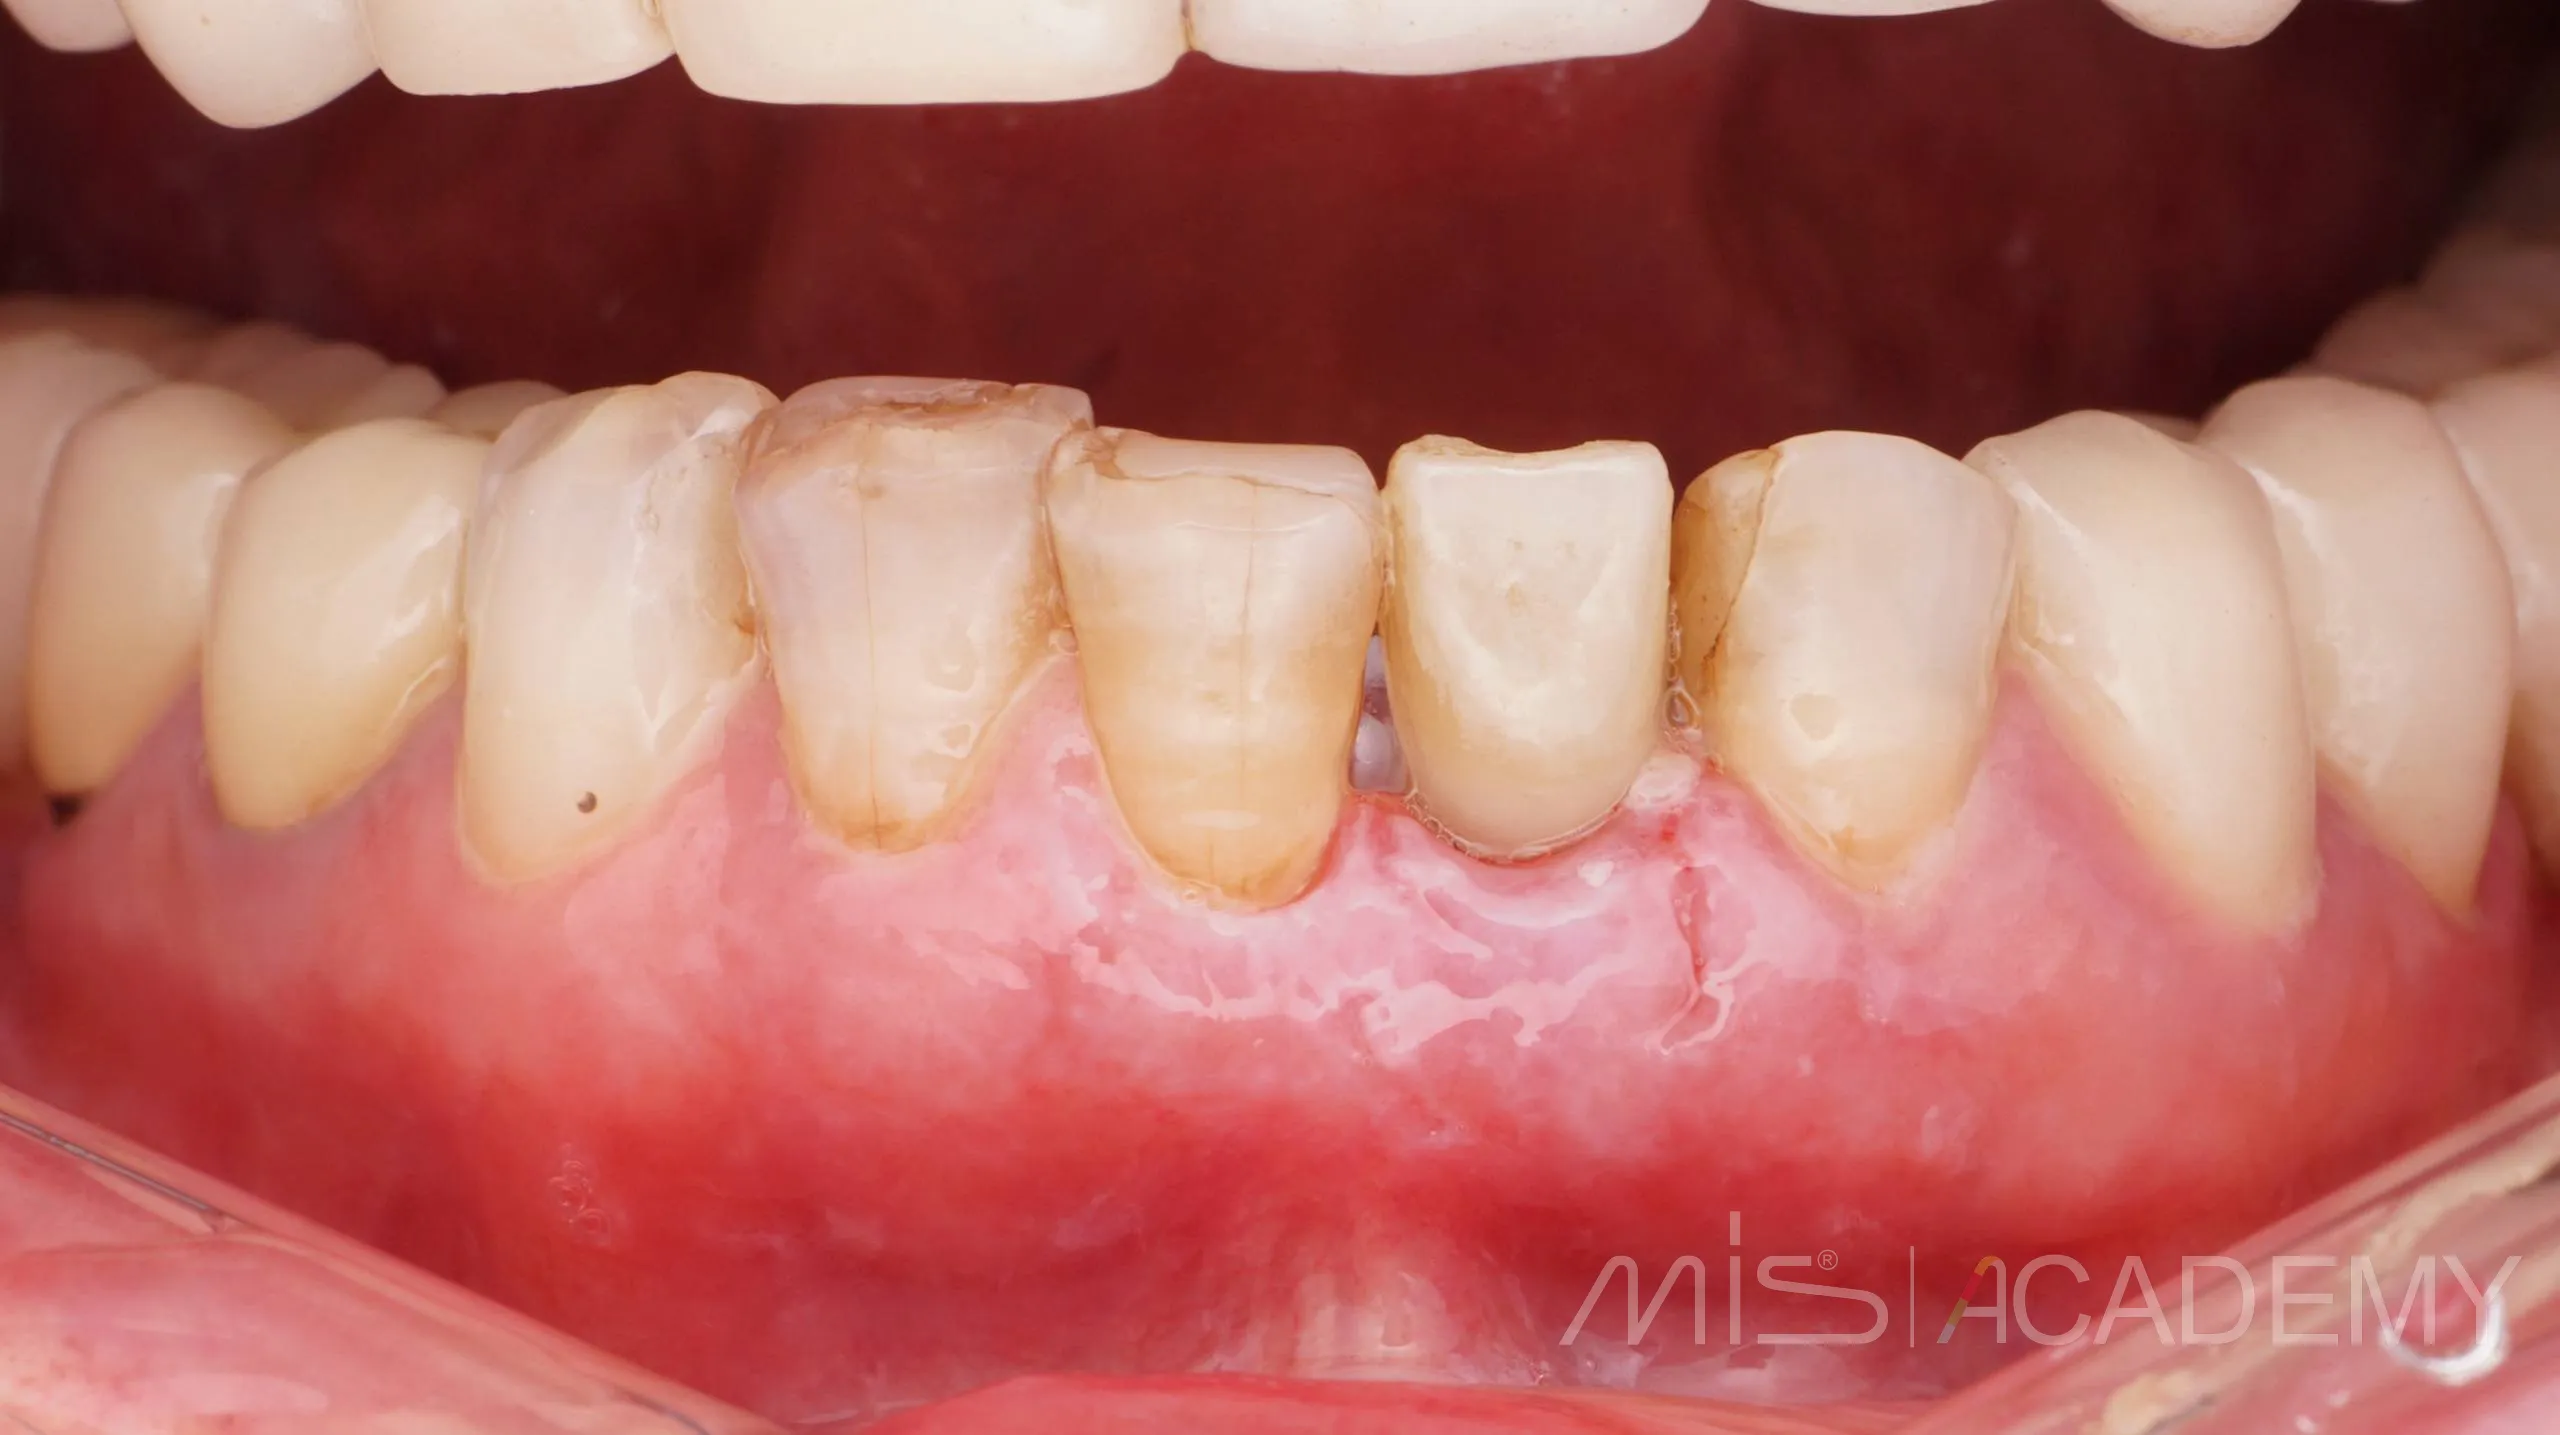

Одномоментная имплантация MIS С1